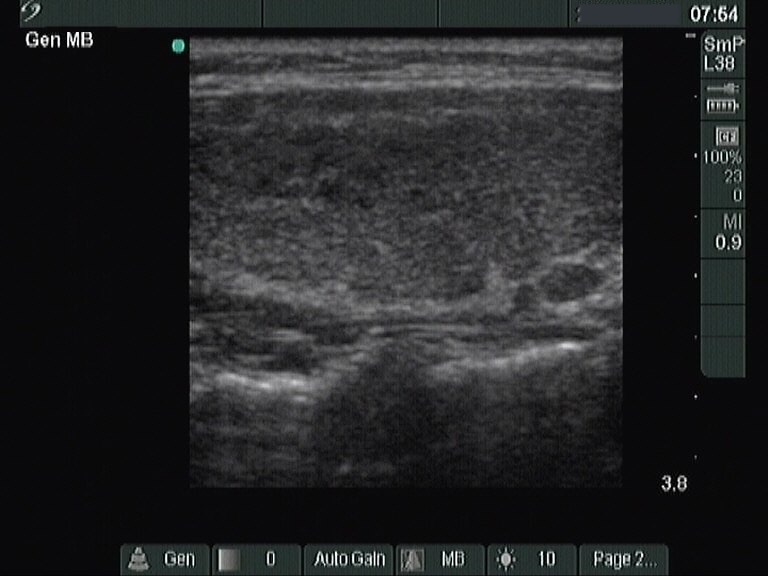

Papillary carcinoma - Case 26. (ultrasonographic picture 2)

Right lobe, longitudinal view.